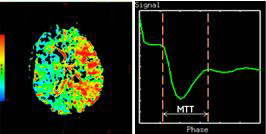

Mean Transit Time

Mean Transit Time (MTT) measures the length of time a certain volume of blood spends in the cerebral capillary circulation.